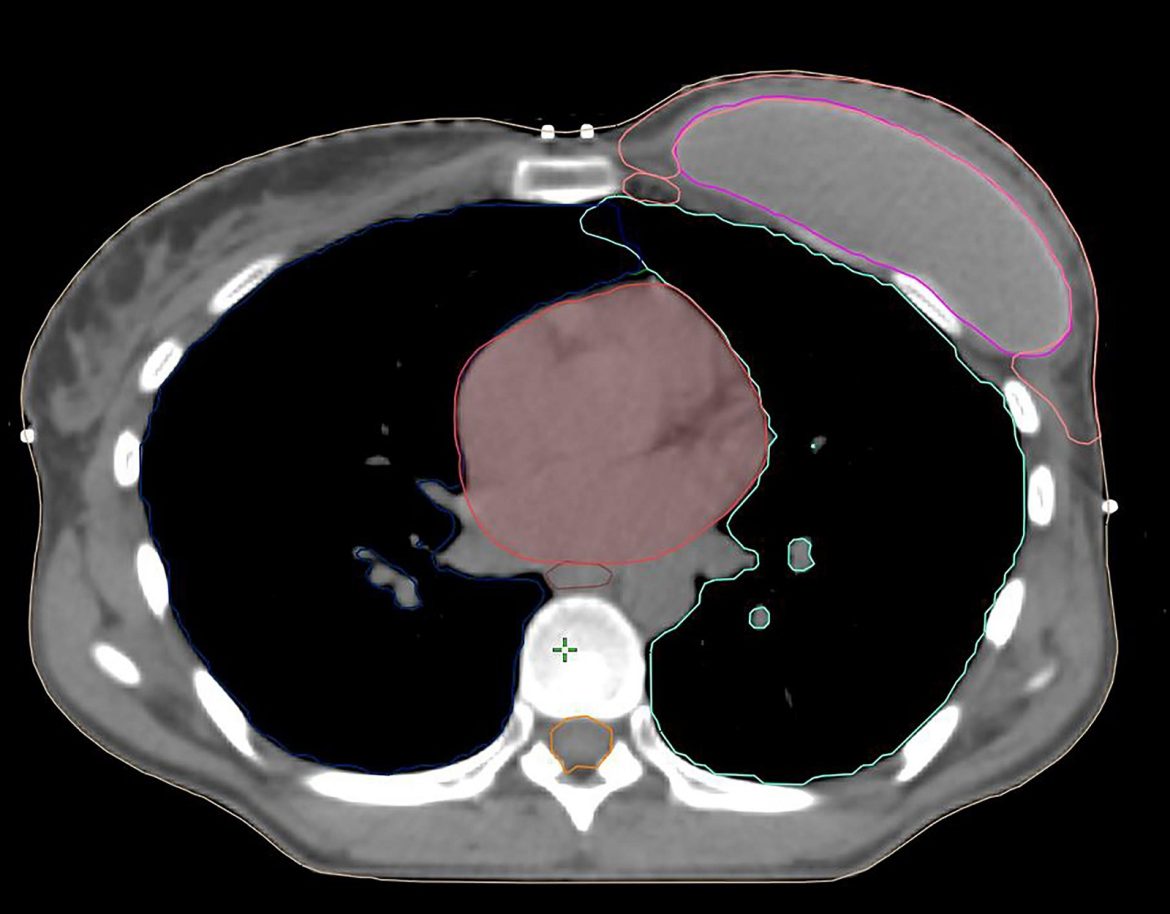

Hình 4a. CTVp_chestwall với chỉ phần trước (Màu đỏ) trong các trường hợp chỉ xạ trị mạng lưới bạch mạch dưới da. Các cơ ngực (Màu vàng) và túi độn (Màu xanh).

Nếu mạc sau tuyến vú không bị xâm lấn bởi ung thư, CTVp_chestwall cho PMRT không bao gồm mạng lưới bạch huyết sâu, do đó, chỉ bao gồm viền tổ chức mô phía trước cơ ngực lớn và túi độn, ngoại trừ ở phía trong, ngoài và dưới, nơi CTV có thể được mở rộng để bao phủ phần thành ngực không được bao phủ bởi cơ ngực lớn trước mổ. Như vậy, phần lớn túi độn có thể được loại khỏi CTVp_chestwall, trong khi các phần thành ngực xung quanh cơ ngực với các dòng chảy bạch huyết vẫn nên được bao phủ. (Hình 4a, b). Lớp cơ ngực phía trên túi độn có thể rất mỏng ở một số người bệnh, vì vậy, thể tích bia lâm sàng thường khó tránh khỏi phải bao gồm ít nhất một phần cơ ngực, nghĩa là giới hạn sau của CTV sẽ là bình diện trước của túi độn.

Với các bệnh nhân có yếu tố bất lợi và/hoặc nếu khối u nằm trong phần nhu mô tuyến sát mạc sau (Diện cắt tiệm cận, u nhuộm màu mực ở mạc sau tuyến vú) không được bao phủ bởi cơ ngực lớn (chủ yếu gặp ở các khối u phần thấp, thường nằm kết cận các xương sườn và cơ liên sườn), chỉ ngăn cách bởi mạc sau tuyến vú, chúng tôi khuyến cáo xác định thêm vùng tổ chức mô giữa thành ngực và túi độn ở phần thấp tính từ vị trí của cơ ngực lớn trước mổ (Lý tưởng nếu được đánh dấu bằng clip trong mổ), như một CTV phía sau tách biệt. (Hình 4B)

Hình 4b. CTVp_chestwall với phần trước (Đỏ) và sau (Xanh biển) trong trường hợp tổ chức bạch huyết dưới da cần được chiếu xạ cũng như phần thành ngực ban đầu không được bao phủ bởi cơ ngực lớn (Vàng). Túi độn sau cơ ngực (Xanh lá cây).

Hình 4c. CTVp_chestwall với phần trước (Đỏ) và sau (Xanh biển) trong trường hợp túi độn trước cơ ngực (Xanh lá cây). Cơ ngực (Vàng)